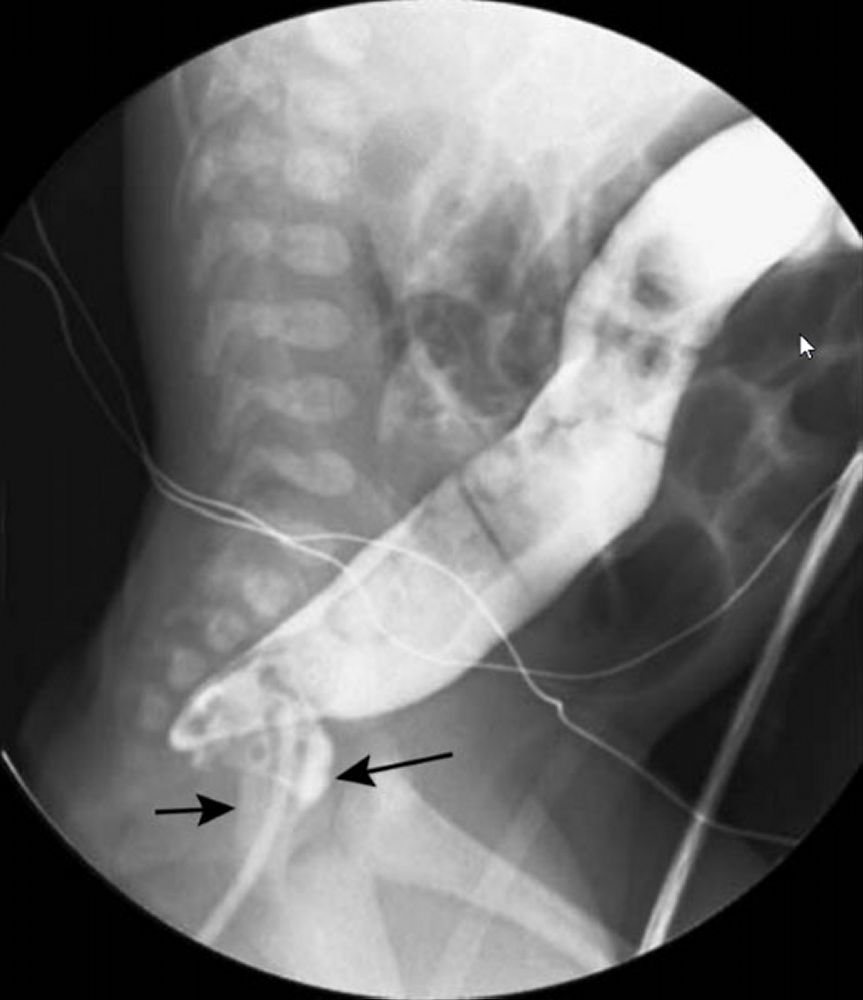

Obstipação em Idade Pediátrica | Concise Medical Knowledge

image size: 810x1080